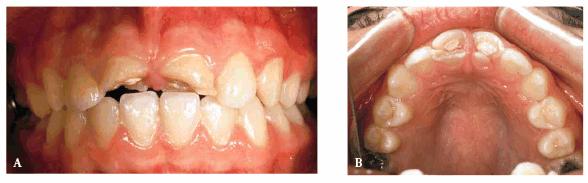

fracture the bonding, then porcelain would be a better alternative (Figur 323s1823d es 18-3A 18-3B 18-3C 18-3D 18-3E and F). In the event that the enamel is

Figur 323s1823d e 18-3A: This young lady fractured her maxillary anterior incisors. Despite numerous bonding repairs, she continued to refracture the teeth. Because she also objected to the incisal translucency, she was treatment planned for three porcelain laminates.

Figur 323s1823d e 18-3B: The initial preparations for the

three porcelain laminates were done with a 0.5-mm depth cutter (Brasseler LVS

System, Brasseler,

Figur 323s1823d e 18-3C: The two-grit diamond is used to reduce the enamel to the predetermined depth cut.

Figur 323s1823d e 18-3D: The final preparations.

Figur 323s1823d e 18-3E and F: Three porcelain laminates were placed on the central incisors and right lateral. The new laminates also achieved the objective to eliminate the incisal translucency.